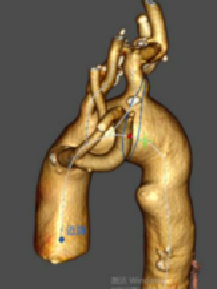

★ 病例1:主动脉弓夹层大裂口

★ 病例2:主动脉弓动脉瘤III型弓

III型弓,血管扭曲,LSA与主动脉呈锐角

术后造影无内漏,各分支形态良好,血流通畅